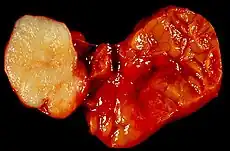

| Parotid gland tumour | |

Salivary gland tumours, also known as mucous gland adenomas[1] or neoplasms, are tumours that form in the tissues of salivary glands. The salivary glands are classified as major or minor. The major salivary glands consist of the parotid, submandibular, and sublingual glands. The minor salivary glands consist of 800 to 1000 small mucus-secreting glands located throughout the lining of the oral cavity.[2] Patients with these types of tumours may be asymptomatic.[1]